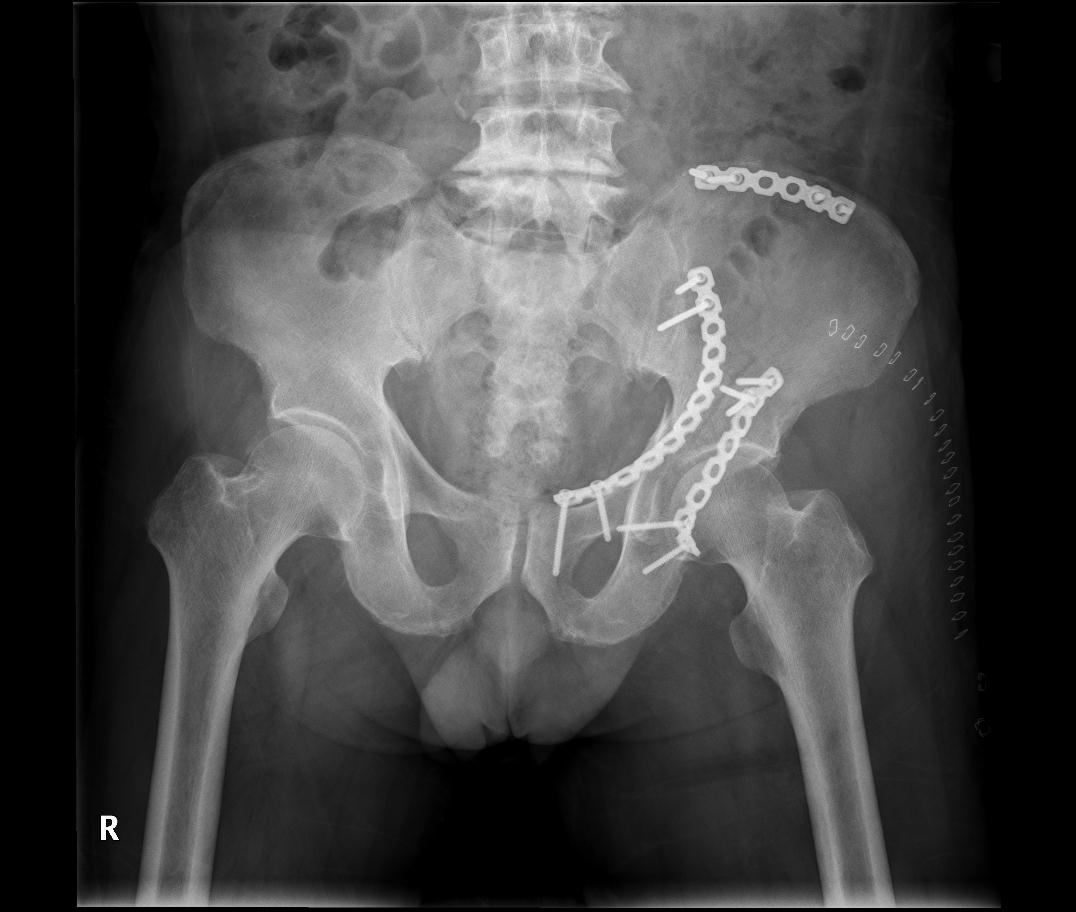

영상 진단: X-ray, CT 스캔, MRI 등을 통해 골절의 정확한 위치와 심각성을 확인합니다.

수술적 치료: 심각한 골반 골절의 경우, 수술을 통해 뼈 조각을 복원하고 고정할 수 있습니다.

골반 골절은 두가지로 볼수 있는데 골반환 골절과 비구 골절로 나누어 집니다.

골반환 골절과 비구 골절은 모두 심각한 부상이지만, 발생 위치와 관련된 특징이 다릅니다.

비구 골절

정의: 비구 골절은 고관절 소켓인 비구에 발생하는 골절입니다. 이 부위는 대퇴골 머리와 결합하여 고관절을 형성합니다.

치료: 대부분의 비구 골절은 수술적 치료가 필요합니다.